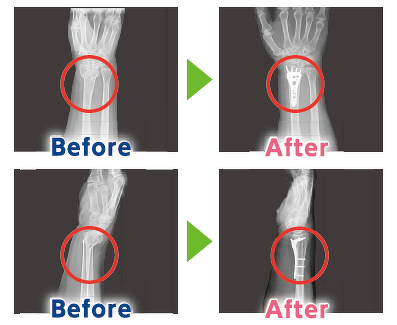

手首・肩の骨折

転倒して手や肩で体を支えた時に起きやすい骨折です。特に手首の骨折は「骨粗しょう症のお知らせ骨折」と呼ばれ、次に大きな骨折を防ぐための重要なサインです。手首は50~60代から骨折が増え、肩は60代以降から受傷が増加します。

手首の骨折は骨粗しょう症の初期サインと言われています。放置すると大腿骨や腰椎の骨折へつながることもあるため注意が必要です。肩の骨折は体重を支える動作に影響します。骨折すると上半身の動作だけでなく、杖をつく、つかまり歩行をする、ベットから起き上がるなどの日常的な動きが難しくなってしまいます。